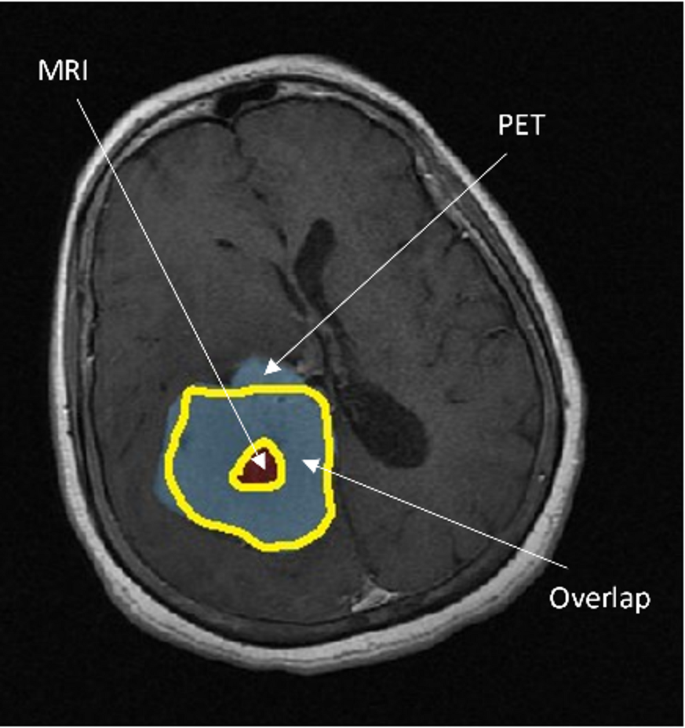

Contrast-enhanced MRI and FLT-PET imaging provide complementary insights into tumor characterization. As illustrated in Fig. 3, the blue areas in the contrast-enhanced MRI image (Fig. 3a) represent active tumor regions identified through increased uptake of the contrast agent. Meanwhile, the red delineated regions in the FLT-PET image (Fig. 3b) highlight tumors with high proliferative activity, offering a distinction from the surrounding tissues. This combined imaging approach enhances the accuracy of tumor detection and characterization, aiding in treatment planning and monitoring.

Sophisticated algorithms were meticulously crafted to extract intricate features from the PET and MRI image datasets, facilitating a comprehensive analysis of the distinctive characteristics and commonalities in tumor features. A central focus of this investigation was to evaluate the degree of tumor volume overlap (referred to as Voverlap) observed in both modalities. Precisely quantifying Voverlap entailed assessing the segmented volume shared by the VPET and VMR images. Furthermore, the analysis encompassed discerning the distinct volumes unique to each modality, denoted as VonlyPET and VonlyMR, respectively. It is crucial to comprehend that PET imaging enables the acquisition of information at an earlier stage in tumor development compared to MRI. Thus, VonlyPET signifies the tumor exhibiting active growth discernible solely through PET imaging, not yet manifest in MRI. Similarly, VonlyMR represents the active and necrotic tumor volume exclusively visualized through MRI imaging. By judiciously amalgamating the segmented volumes attributed to either VPET or VMR or both, their volume of tumor in combination, portrayed in MR and PET images can be ascertained. This comprehensive information significantly contributes to a more profound understanding of tumor growth dynamics and provides crucial insights into potential avenues for treatment optimization. The segmentation of tumor volumes across PET and MR modalities provides valuable insights into spatial overlap and modality-specific differences. As illustrated in Fig. 6, the segmented volumes for PET and MR are displayed, highlighting their spatial overlap (Voverlap) as well as unique volumes identified exclusively by each modality (VonlyPET and VonlyMR). This comparison underscores the complementary nature of PET and MR imaging for comprehensive tumor characterization.

Figure 7 exhibits a meticulously selected axial slice of the brain, ingeniously captured utilizing MRI with contrast enhancement. This striking visualization distinctly showcases the derived tumor volumes, meticulously delineating the distinct regions exclusively revealed through PET imaging (referred to as PET-only), the unique areas solely visible in MR imaging (referred to as MR-only), and the captivating overlapping tumor volumes that are prominently observed in both modalities. This comprehensive illustration provides a profound visual representation of the intricate interplay between PET and MR imaging in capturing and characterizing tumor volumes, thereby enriching our understanding of the multifaceted nature of these tumors.